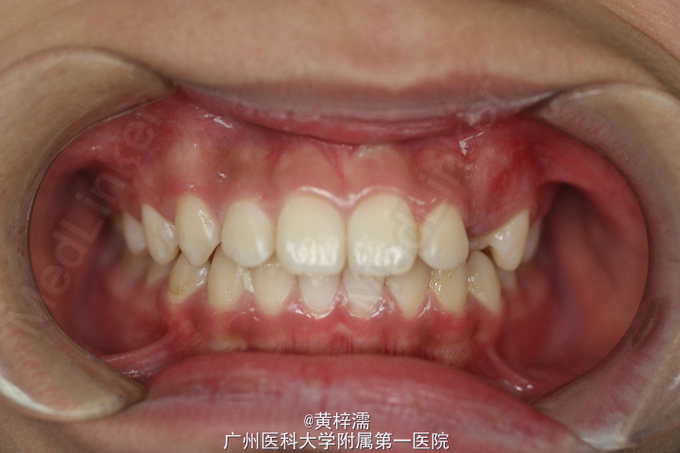

面部基本对称,无露龈笑,笑容不自然。直面型,面中1/3高度与面下1/3高度基本相等。下颌后缩,颏部发育稍不足。上中线与面中线一致,下中线稍右偏0.3mm。左侧磨牙关系中性,无尖牙关系。22,24间前庭沟下方可见鼓起,扪及23,磨牙覆盖正常。右侧磨牙关系中性,尖牙关系1/4远中,磨牙覆盖正常。上牙弓卵圆形,23缺牙间隙8.5mm,13宽度为8.5mm。口腔卫生可,未见牙体、牙周疾病,颞下颌关节检查未见异常。